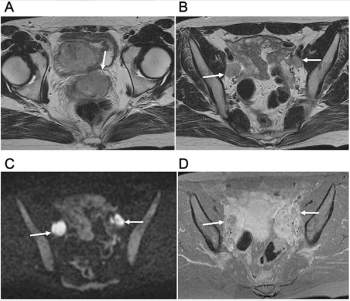

Diffusion-weighted imaging may be useful as a safe and effective screening tool to supplement mammography in women with dense breast tissues.